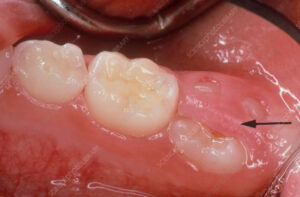

◽️萌出性歯肉炎について

参考:sciencephoto

萌出性歯肉炎とは、新しく生えてくる歯が歯ぐきを通過する際に生じる一時的な炎症です。腫れや発赤、かゆみといった症状が現れることがあります。

乳歯が生え始めるときや永久歯に生え変わるときによく見られる現象で、一時的なものであることが多いです。

この際にプラーク(歯垢)や食べかすなどが溜まりお口が不衛生な状態ですと炎症がひどくなったり、痛みが強くなったりしますので丁寧にお口のケアをするようにしましょう。

症状が長引くか強い場合は、歯科医院に受診してください。